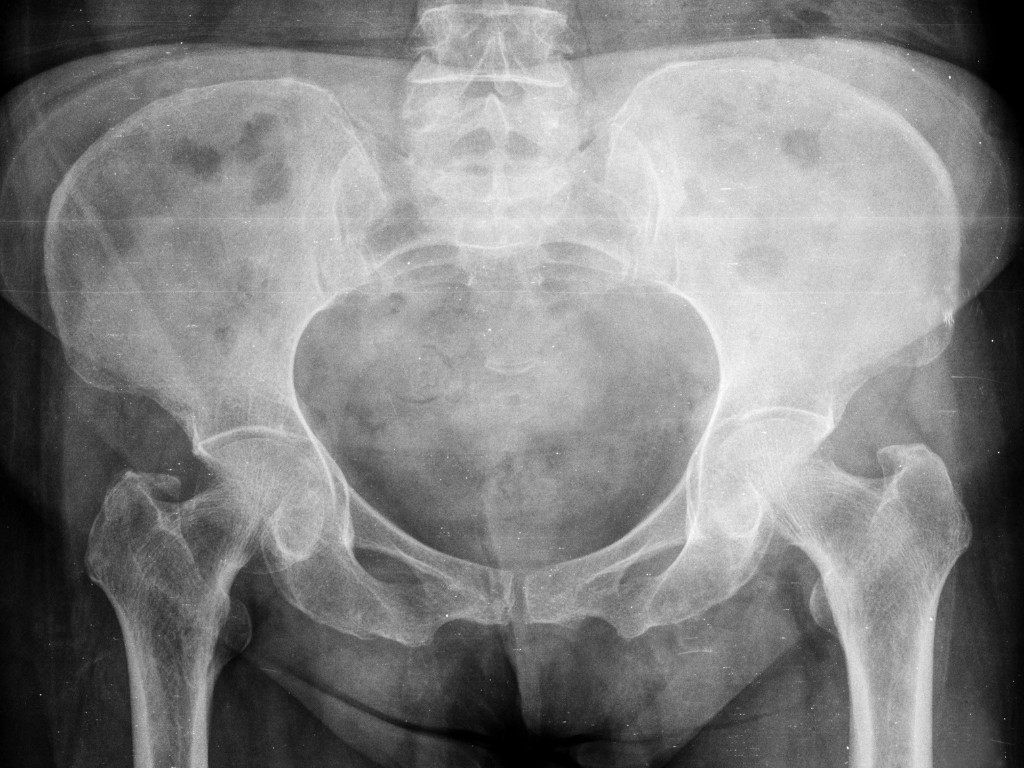

Clear, advanced diagnosis: Using advanced imaging like MRI and X-ray, Dr. Mehta identifies the underlying damage, so your treatment is precise.

Step 3: Investigations

To get a detailed view of your hip health and find the underlying issue, Dr. Mehta may recommend imaging tests like X-rays or an MRI.